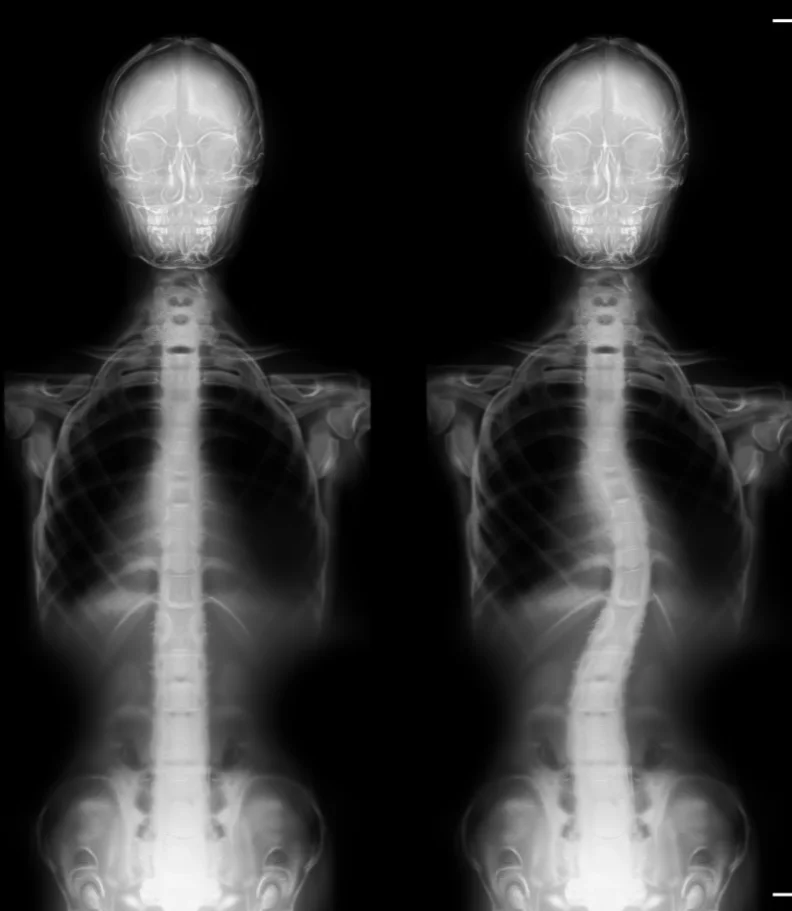

Are you in search of the finest chiropractor in Daytona Beach, dedicated to caring for scoliosis? Typically, scoliosis begins as a subtle curvature in the spine that gradually intensifies over time. A scoliosis diagnosis occurs when the spine deviates more than ten degrees to either the right or left when facing a medical examiner. As scoliosis advances to more severe stages, it can bring about significant health consequences.

Scoliosis manifests as an abnormal bend or curve in the spine, deviating from the ideal vertical alignment of a healthy spine. The exact origin of this curve can often be elusive. In its early stages, it may begin as a minor bend due to a single vertebra's misalignment. Over time, the body compensates by developing musculature that continues to pull the spine into lateral curves to maintain a level head position.

Often, parents or close associates are the first to notice scoliosis, as the shoulders and pelvis no longer appear level. A thorough physical examination assesses gait and utilizes visual and manual evaluations to determine the extent of spinal curvature. An Adams Position Test, involving the patient bending forward as far as possible, can reveal the presence of an issue. If a noticeable curvature is detected, an X-ray will be employed to assess the severity of scoliosis.